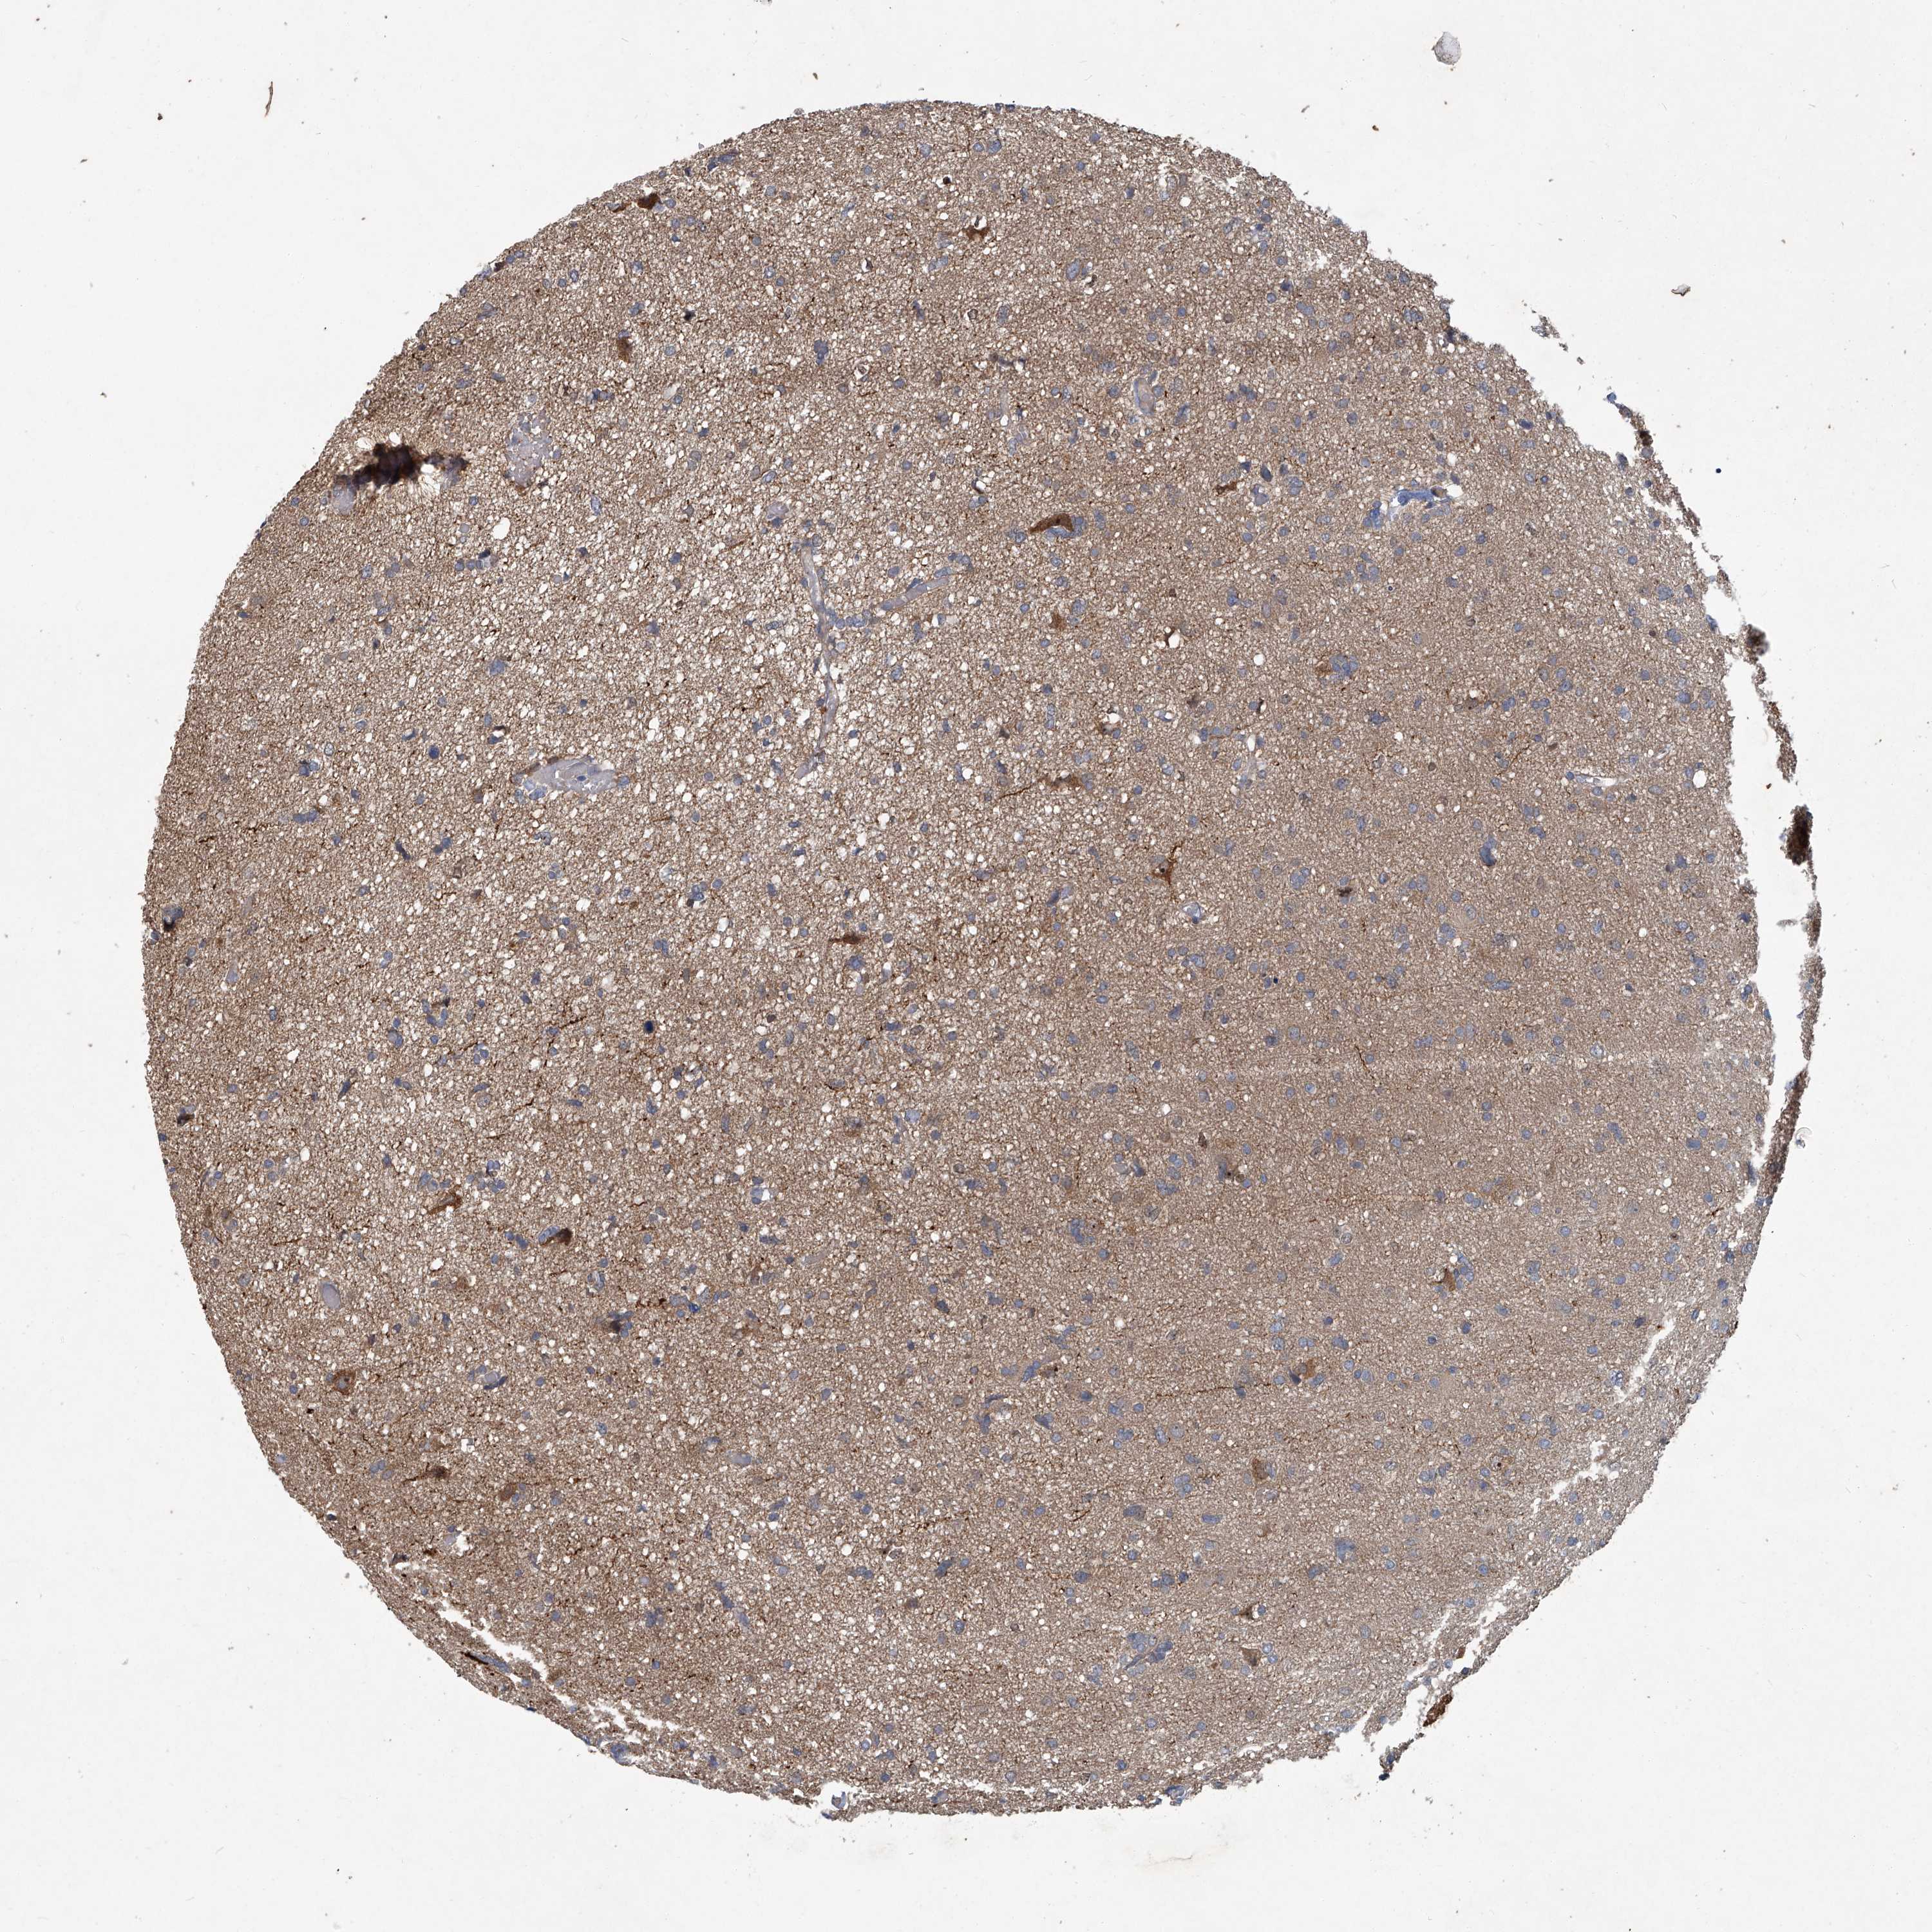

GLIOMA - Protein expressioni

A mouse-over function shows sample information and annotation data. Click on an image to view it in a full screen mode. Samples can be filtered based on level of antibody staining by selecting one or several of the following categories: high, medium, low and not detected. The assay and annotation is described here.

Note that samples used for immunohistochemistry by the Human Protein Atlas do not correspond to samples in the TCGA dataset.

Antibody stainingi

Antibody staining in the annotated cell types in the current human tissue is reported as not detected, low, medium, or high, based on conventional immunohistochemistry profiling in selected tissues. This score is based on the combination of the staining intensity and fraction of stained cells.

Each image is clickable and will lead to virtual microscopy that enables deeper exploration of all samples and also displays staining intensity scores, fraction scores and subcellular localization as well as patient and tissue information for each sample.

Antibody HPA029642

Antibody HPA029643

Glioma, malignant, High grade

Glioblastoma, NOS